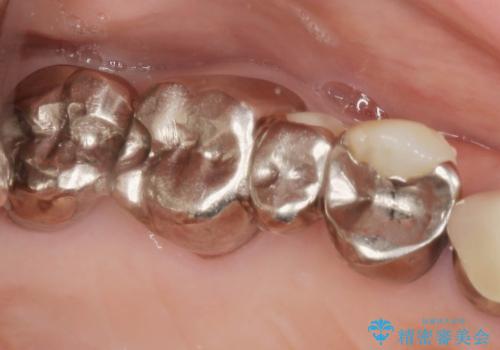

セラミック・インプラント治療を含む包括歯周病治療

- 「銀歯だらけの歯を変えたい。他院で歯周病と指摘されたがクリーニング以外何もしてくれない。」、とセラミック治療歯周病治療を希望され来院されました。

検査の結果、感染根管や欠損、歯周病により残すことのできない歯、等多々問題が認められます。

残すことのできる歯できない歯を選別し、欠損部にはインプラントによる咬合機能の回復、保存できる歯には歯周病治療・根管治療を行う治療計画としました。